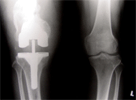

Healed but developed malunion and knee osteoarthritis, treated with intrarticular correction and knee replacement

Post

Op

surgery : Good restoration alignment and pain relief